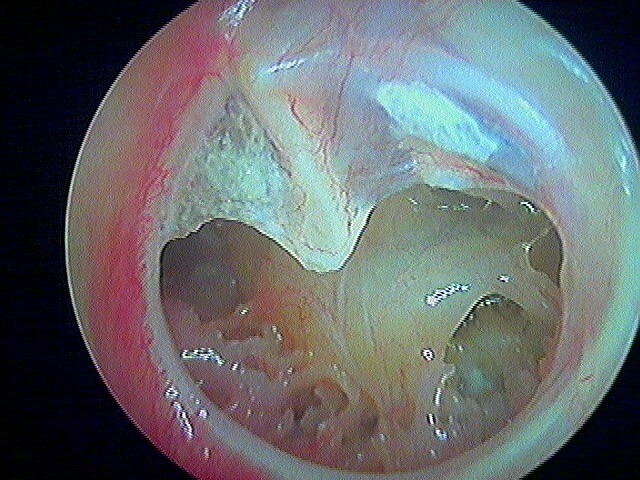

9 OTITE MOYENNE CHRONIQUE (OMC) NON CHOLESTÉATOMATEUSE

Perforation , otorrhée à répétition, otite muqueuse dans la caisse, lyse ossiculaire, rétraction tympanique. La limite entre l'otite atéléctasique perforée et l'otite moyenne chronique non cholestéatomateuse est souvent ésotérique...